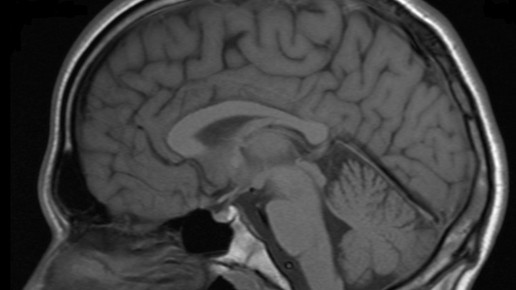

Die Forschergruppe um Kyle Ratner, Amanda Kaczmarek und Youngki Hong hatte verschiedene Studien der vergangenen Jahre zusammengetragen und in der Summe ausgewertet. Bereits Anfang 2000 hatten Wissenschaftler untersucht, ob neuronale Regionen, die an der Wahrnehmung von Schmerzen beteiligt sind, auch auf soziale Abgrenzung reagieren. Die Schnittstelle zwischen Sozialpsychologie und kognitiver Neurowissenschaft machten die Forscher mittels funktionaler Magnetresonanztomographie (fMRT) sichtbar. Die Teilnehmer absolvierten ein virtuelles Ballspiel und wurden im Spielverlauf ausgeschlossen. Die Bildgebung konnte zeigen, dass die gleiche Hirnregion für den emotionalen Schmerz in Folge des Ausschlusses angesprochen wurde wie sonst für körperliche Schmerzen.